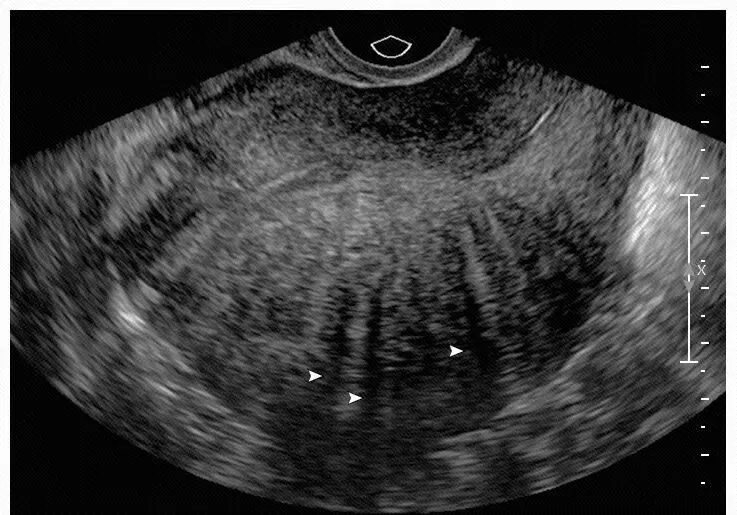

子宫腺肌病典型超声特征示意图

不对称增厚(A)、囊肿(B)、高回声岛(C)、扇形阴影(D)、子宫内膜线下的线状和芽状高回声(E)、病灶内横贯的血管(F)、不规则连接区(G)和连接区中断(H)。

子宫增大,子宫后壁比前壁肌层厚,后壁肌层呈栅栏样改变(箭头示)